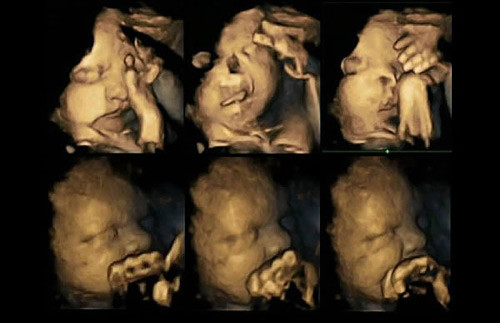

Tiến sĩ Nadja Reissland nghiên cứu những hình ảnh siêu âm 4D của hàng nghìn hành động rất nhỏ của thai nhi, đặc biệt ở những bà mẹ hút thuốc lá. Trong khi những bà mẹ không hút thuốc thường thai nhi không có những biểu hiện như trên.